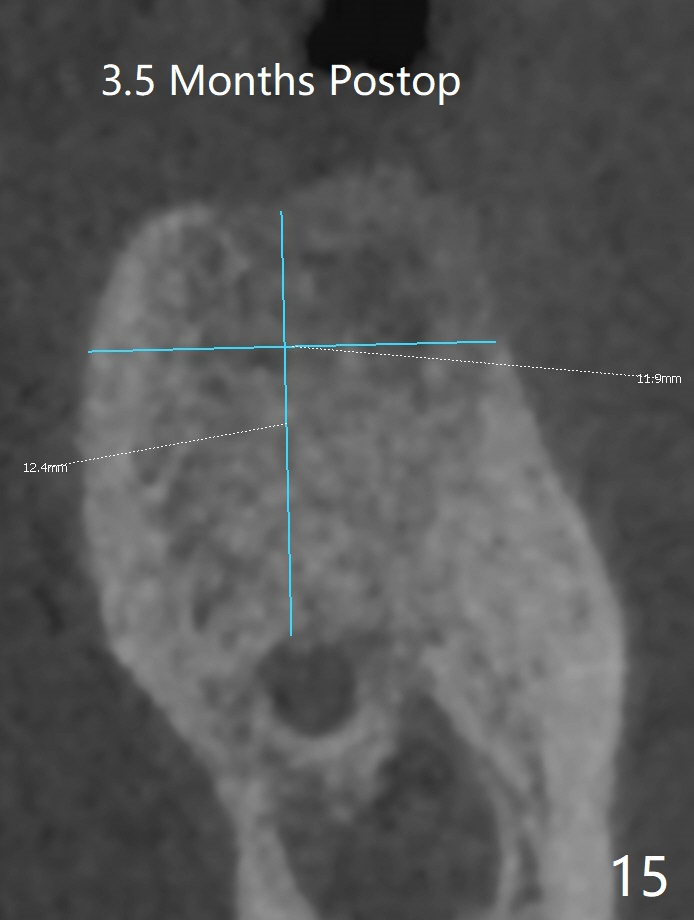

When the patient returns for #15 comp, the bone resorption and swelling at #19 are worse than those 3 years ago (Fig.1,2). After debridement, the mesial socket is large, while the septum is thin, irregular and with undercut (Fig.3). It seems difficult to obtain primary stability for an immediate implant. Vanilla bone and cortical bone hydrated with GEM21 S are placed for socket preservation (Fig.4,5), followed by 12x12 mm BioXclude and 4/0 PGA. In fact the bone height is limited for an immediate implant (Fig.6 (5x10 mm)). There is not enough bone in the septum for primary stability (Fig.7 (cross section of 3D image; L: lingual)). The socket heals 16 days postop (Fig.8). It appears that the granulation tissue is covered by a thin layer of granulation tissue (Fig.9 *), while the membrane remains in place (M). In fact the bone graft remains in the soft tissue zone as well as the hard tissue one (Fig.10). In spite of no apparent loss of bone graft (Fig.4,10), the graft seems to shrink in height 3.5 months postop (Fig.11), while the crest decreases (compare Fig.1 and 11). The keratinized gingiva is wide, but the alveolus reduces in width (Fig.12). The buccal crestal bone is lost 3.5 months postop (Fig.13).